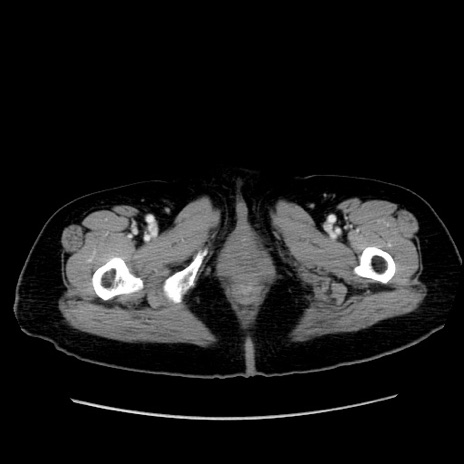

症例19(横断像)

【症例】80歳代女性

【主訴】下腹部痛

【現病歴】約8時間前より下腹部痛の出現あり、救急外来受診。

【既往歴】両側付属器切除

【身体所見】意識清明、下腹部正中に手術痕あり、その部位に一致して圧痛と反跳痛あり。腸蠕動音は亢進。

【データ】WBC 9300、CRP 0.15